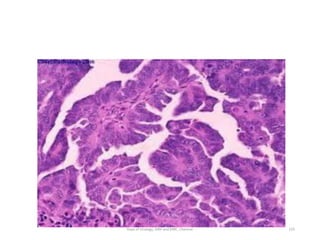

HGPUC

• Fused papillary stalks with high-grade

cancer in the urothelial layer.

• Disordered growth pattern,

numerous mitotic figures

pleomorphic cells

with exaggerated nuclei.

• Over 80% of high-grade cancers will

invade the underlying stroma